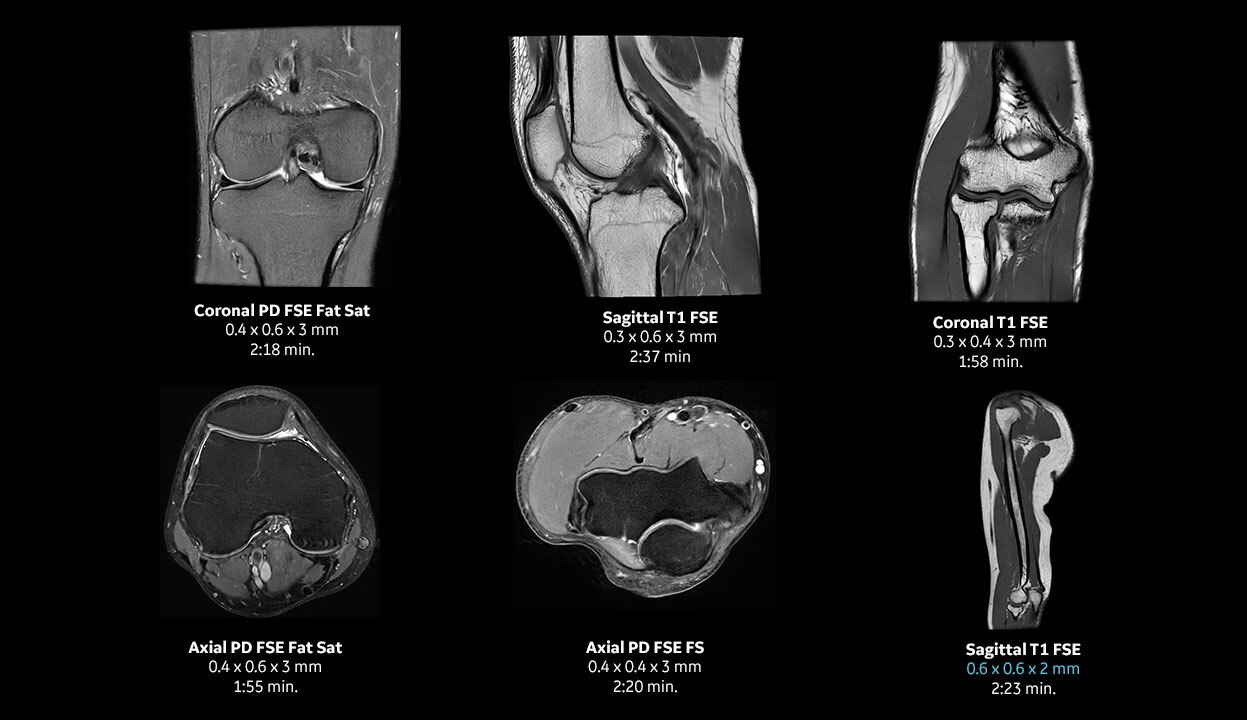

With access to the latest advanced AI technology, you can scan all anatomies and achieve pin-sharp images. Our pioneering Deep Learning-based reconstruction algorithm AIR™ Recon DL accelerates scan time and puts patients at ease.